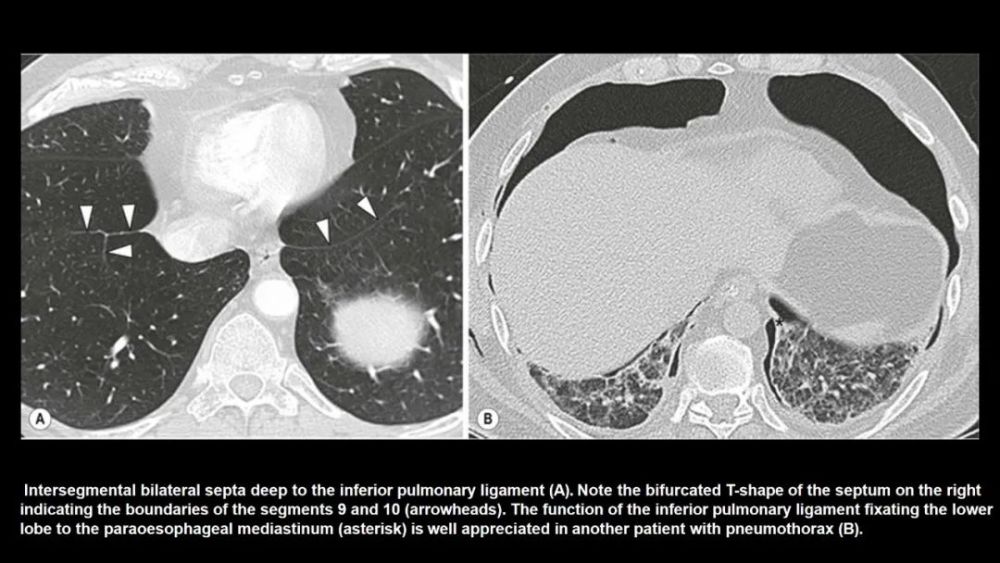

Inferior accessory fissure

Twining’s line , 分隔下叶的内侧基底段

CT上的检出率:12% , 前位胸片显示率:5~8%R:L=5:1;多为不完整的 , 0.5~2cm